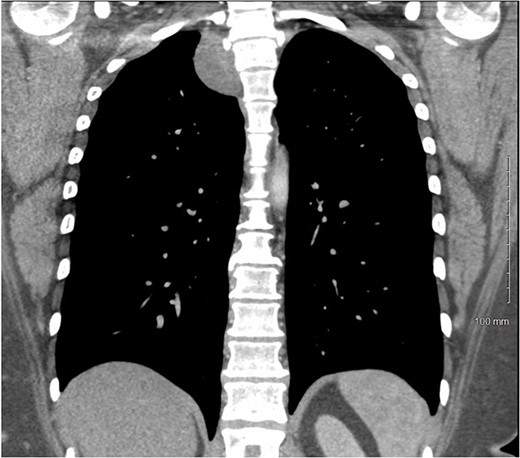

CT chest with IV contrast coronal view of right T2-T3 paravertebral mass.